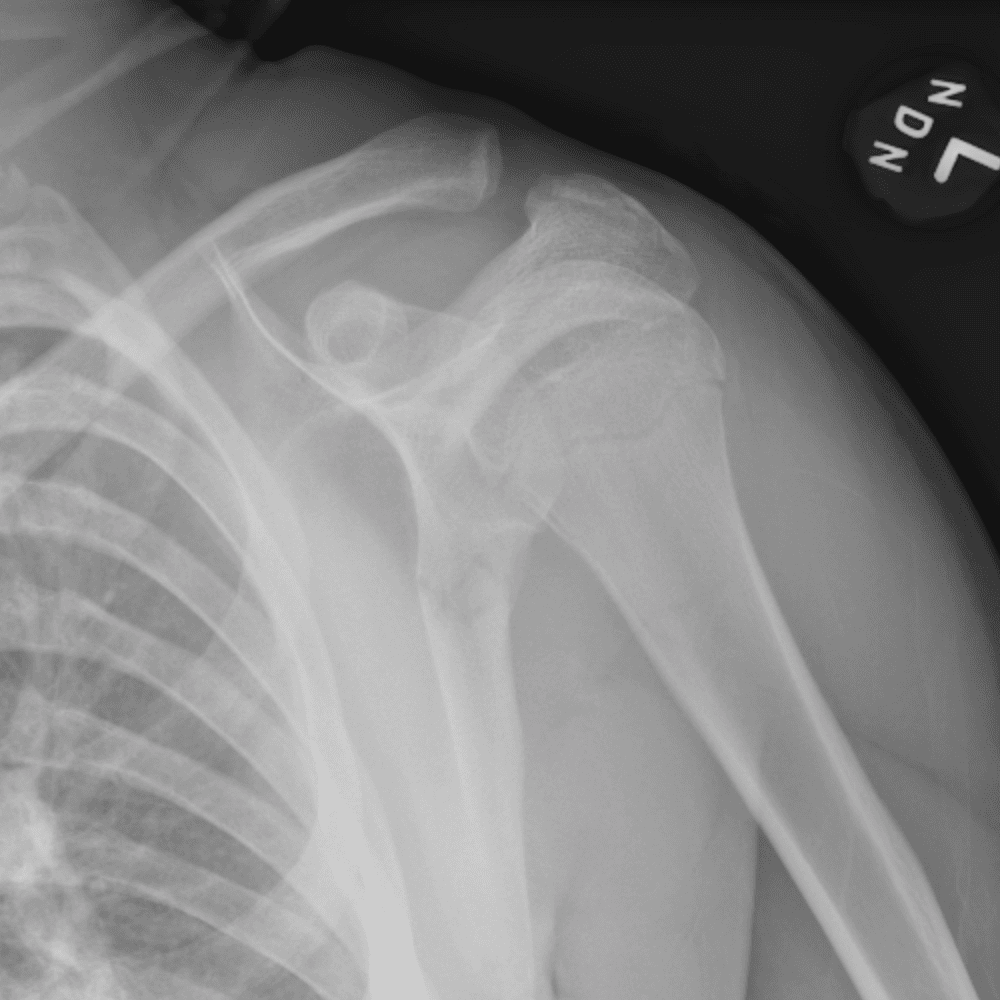

Simuliert den Dienst durch subtile oder schwierige Fälle und einige Normalbefunde.

30 Fälle